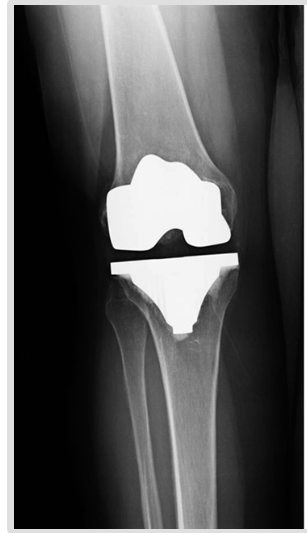

Primary Total Knee replacement is a surgery where the damaged knee joint is replaced with an implant or a prosthesis made of metal or plastic components. Most of the primary total knee replacement surgeries are successful, over time certain problems like implant wear, infection, instability, stiffness, fractures and loosening may require a revision procedure to replace the original components.

The revision knee replacement surgery involves repairing the damaged parts and removing and replacing a total or partial knee implant (prosthesis) with a new one.